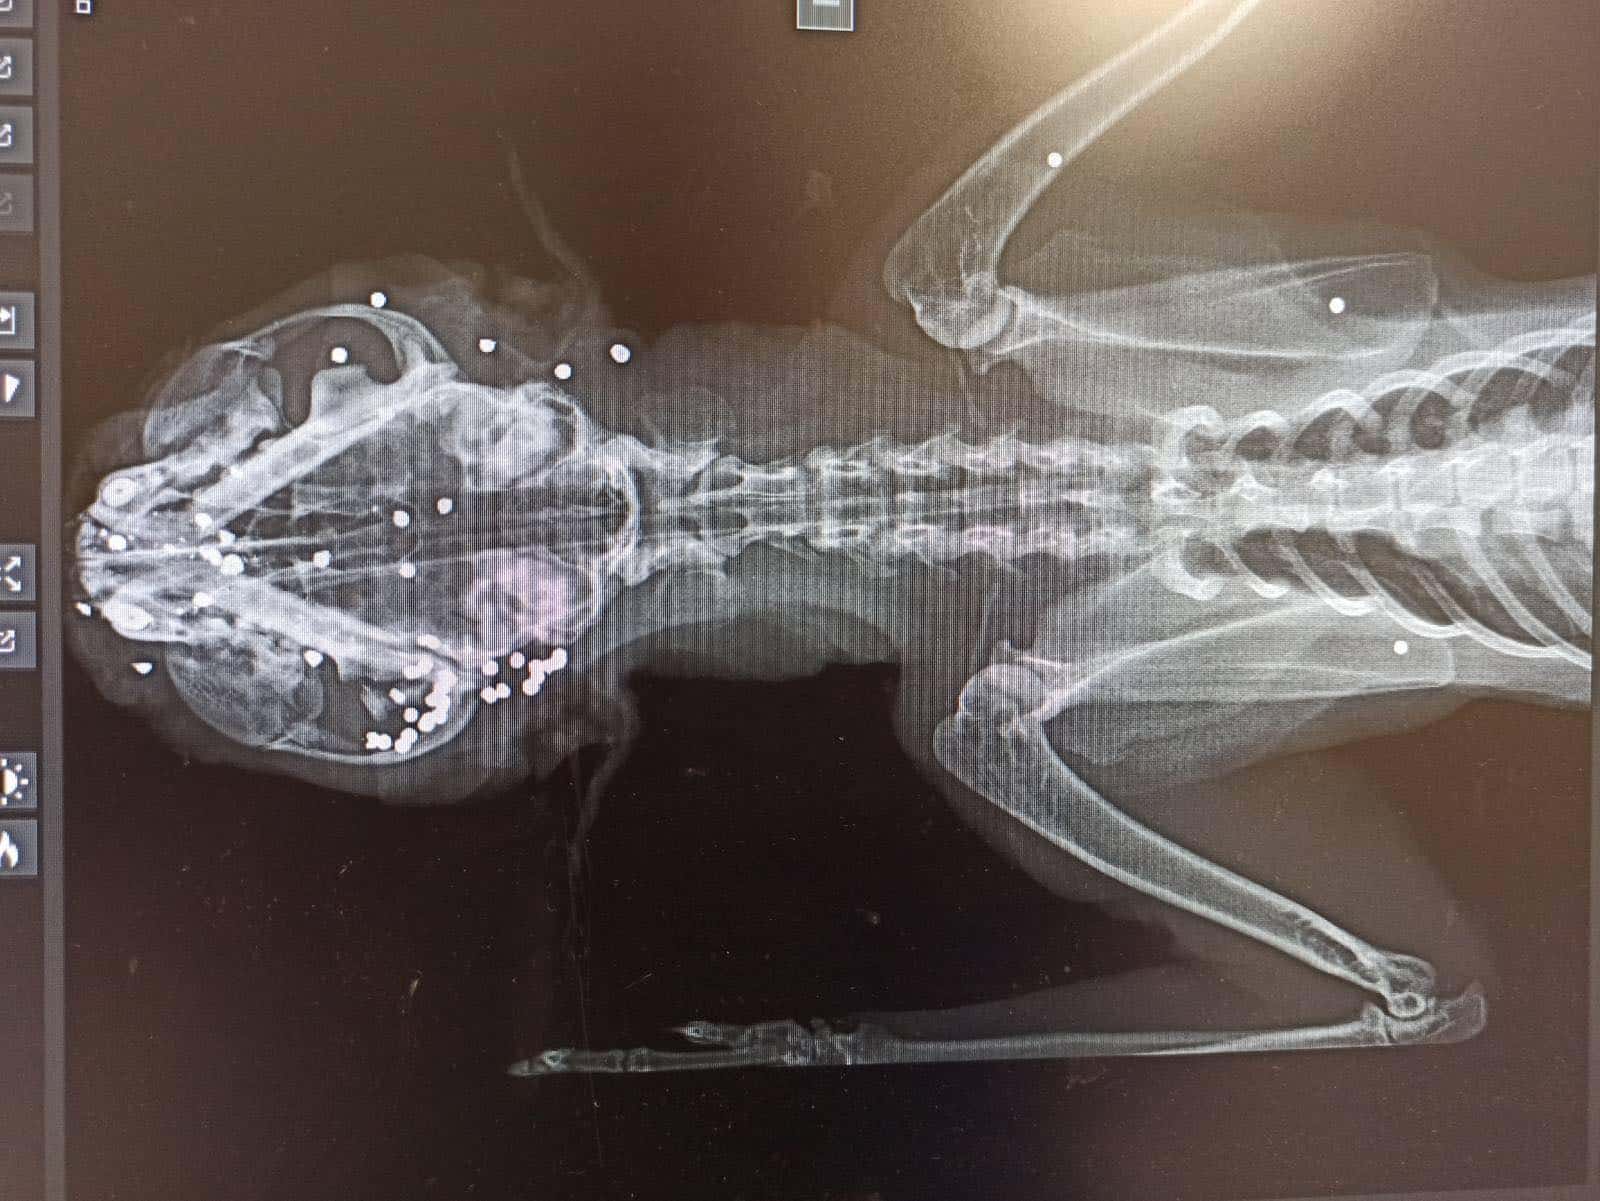

Το γατάκι που ήταν σε ημικωματώδη κατάσταση παρουσίασε υποθερμία και χρειάστηκε άμεση χορήγηση υγρών, συνεχή θέρμανση και χορήγηση ηλεκτρολυτών και παυσίπονων. Όλο του το σώμα (ήταν διάσπαρτο από σφαιρίδια (πρόσωπο, θώρακας και κοιλία).

Παρέμεινε στην ιδιωτική κτηνιατρική κλινική επι 19 μέρες. Παρόλο που το γάτακι έχει ξεπεράσει τον κίνδυνο θα παραμείνει τυφλό. Εχει ήδη γίνει εξόρυξη αριστερού οφθαλμού. Δυστυχώς και το άλλο ματάκι είναι τυφλό.